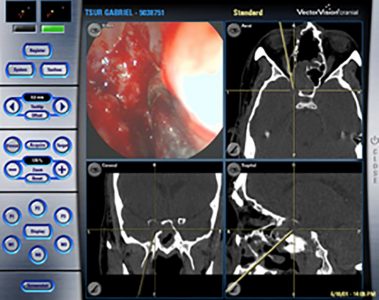

מערכת ניווט בניתוחים אנדוסקופים

מערכת ניווט ("GPS") בניתוחים אנדוסקופים של האף והסינוסים לעיתים, גם הכיסוי התרופתי הרחב והממושך ביותר אינו פותר את תסמיני החולה הלוקה בסינוסיטיס. במצבים אלה יש לשקול ניתוח אנדוסקופי של האף ומערות הפנים (ESS – Endoscopic Sinus Surgery), אשר כבר ביסס את מעמדו כטיפול הכירורגי המקובל והמועדף לבעיה רפואית זו. הניתוח כולו מבוצע דרך הנחיריים, ללא צורך […]